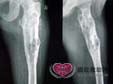

X线所见 表现为邻近生长骺板的透明病变,在成人可侵犯骺端,所在骨的轮廓中度膨胀,皮质骨变薄,可...